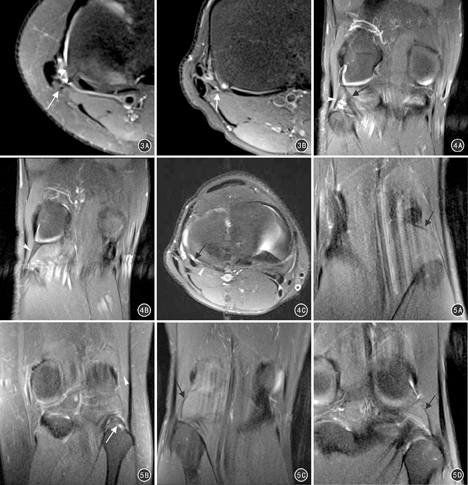

冠状位、斜矢状位PDWI序列MRI可清晰显示其走行,腘腓韧带连接腘肌及腓骨头,起自腘肌肌肉肌腱连接部附近,向远外侧延伸,止于腓骨茎突内侧前下方接近胫腓关节处。MRI表现为自腘肌肌肉肌腱连接部向远外侧延伸,至腓骨茎突内侧前下方或腓骨头的扁平扇形低信号结构(图2),本组出现弓状韧带及豆腓韧带的膝关节均显示腘腓韧带行于其深面(图3);冠状面显示腘肌与腘腓韧带呈一锐角(图2A),这与PLC的其他结构均近乎垂直走向的特点有所不同,可以作为辨识该韧带的一个特征。

弓状韧带及豆腓韧带的尸体解剖及MRI显示率及大小多变[6,24]。本研究显示,弓状韧带起自腓骨头尖,向上走行从后面越过腘肌腱,然后在腓肠肌外侧头起点下方与股骨外侧髁后外侧的关节囊相融合。另有尸体解剖显示,弓状韧带更细微的分为内、外侧支似"Y"形,外侧支(或垂直支)向上沿关节囊延伸至股骨外侧髁,内侧支(弓形支)向内上跨过腘肌腱与后关节囊融合[12,25];然而,本研究未观察到此更细微的结构,可能因MRI对微小结构的显示还存在一定限制。Raheem等[24]研究报道,豆腓韧带出现率35.7%(5/14),与本组显示率(37.5%)相似;同时,Raheem等还认为部分豆腓韧带与弓状韧带融合时其强度要比两者独立存在时大大加强。弓状韧带及豆腓韧带损伤后诊断常常较为困难,临床上绝大部分被其他膝关节损伤所掩盖而无法检出,而MR冠状位PDWI序列可观察两者的形态及信号而提示其损伤的可能性,当后外侧关节囊周围信号增高可提示损伤,弓状韧带腓骨茎突止点撕脱经常与股二头肌短头直接臂的撕脱同时发生[26],故当合并腓骨茎突或股二头肌等更多后外侧关节囊周围结构损伤时则更易诊断。